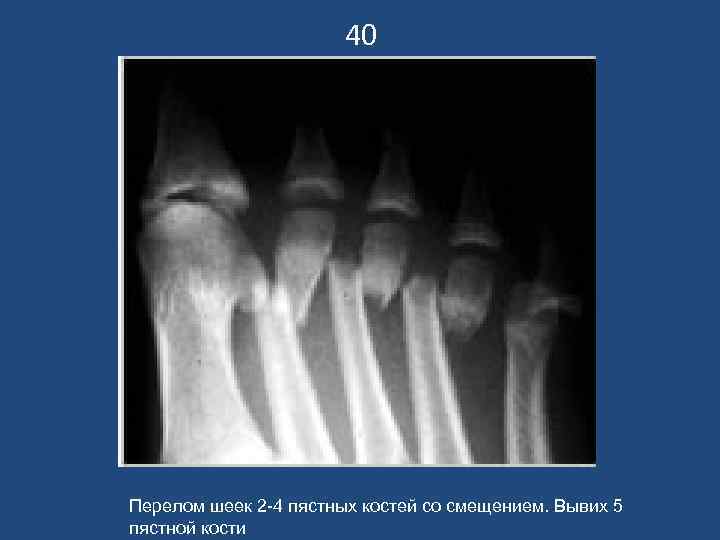

40 Перелом шеек 2 -4 пястных костей со смещением. Вывих 5 пястной кости